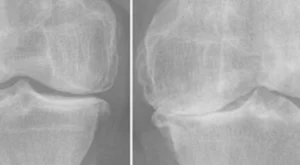

Diz Protezi Ameliyatı: Hastalar İçin Kapsamlı Bilgilendirme

Diz eklemi, günlük yaşamda en çok kullanılan eklemlerden biridir. Yürümek, merdiven çıkmak, oturup kalkmak gibi basit hareketlerin bile sağlıklı bir diz yapısına ihtiyacı vardır. Ancak yaşlanma, kireçlenme (osteoartrit), romatizmal hastalıklar veya geçmişte geçirilen travmalar diz ekleminde ciddi hasara yol açabilir. Bu durum, şiddetli ağrıya, hareket kısıtlılığına ve yaşam kalitesinde belirgin düşüşe sebep olur. İlaç ve fizik tedavi yöntemleri fayda etmediğinde ise en etkili çözüm diz protezi ameliyatıdır.